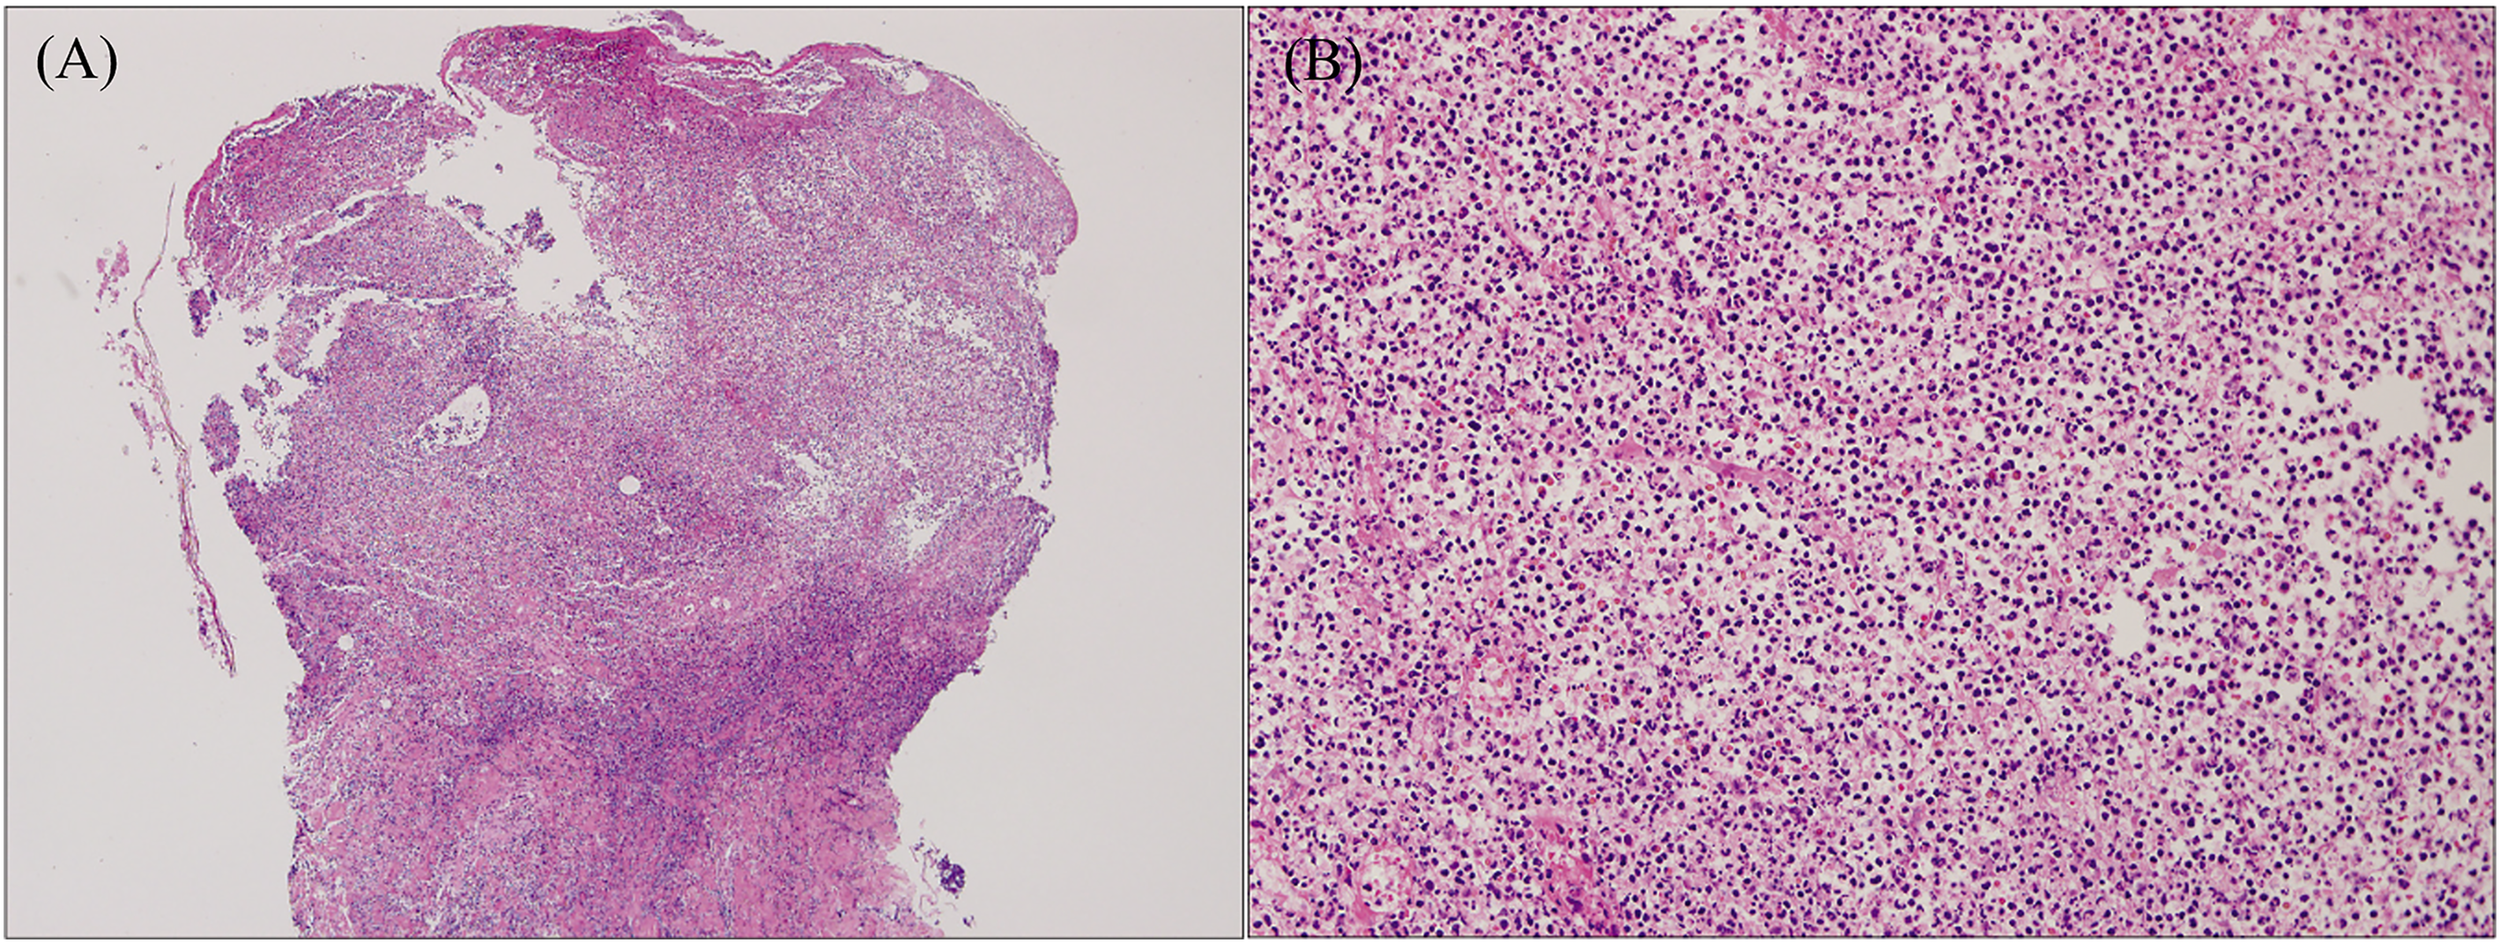

Although EN is associated with the pathological processes of a variety of diseases, histopathological examination of the lesion site demonstrates typical septal panniculitis without vasculitis, regardless of the underlying etiology (83, 84). It usually changes with the phase of the disease (85). The early lesions show interlobular septal edema with mixed inflammatory cell infiltration, including lymphocytes, histiocytes, eosinophils, and numerous neutrophils (Figure 5). Inflammation is usually concentrated in the periphery of the septa. The late lesions present thickening and fibrosis of the septa infiltrated by lymphocytes, histiocytes, multinucleated giant cells, and a few neutrophils. Inflammation extends to the periphery of the fat lobules (82, 85, 86). Miescher’s radial granulomas can also be observed (84) (Figure 5). Miescher’s radial granulomas present with nodular aggregations of small histiocytes and macrophages radially arranged around star-shaped cleft-like spaces, which are typical characteristics of EN (82, 83, 86).

Figure 5 Histopathology of EN shows septal panniculitis and a mixed inflammatory infiltrate predominantly composed of lymphocytes, histiocytes, and neutrophils (H&E staining, ×40). Inset: Miescher’s radial granuloma (H&E staining, ×200). Reproduced with permission from (84). © 2016 The International Society of Dermatology.